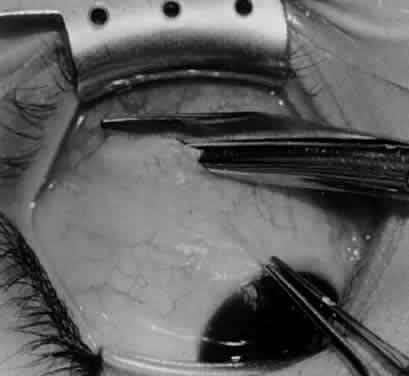

Fig. 33. A 6-0 Vicryl suture is placed in the inferior oblique muscle in preparation for anterior transposition. A Green muscle hook is placed beneath the inferior rectus muscle.

Fig. 34. The eye is retracted nasally with a Green muscle hook. The anterior suture is placed just anterior and temporal to the insertion of the inferior rectus muscle. The posterior suture is applied about 10 mm temporal to the inferior rectus muscle on a line that would be continuous with the inferior rectus insertion if it were extended temporally.

Fig. 35. The suture is tied, and the inferior oblique muscle is in the position for anterior transposition. The inferior rectus muscle is retracted nasally on the Green muscle hook, and the Desmarres lid retractor is placed inferior temporally.